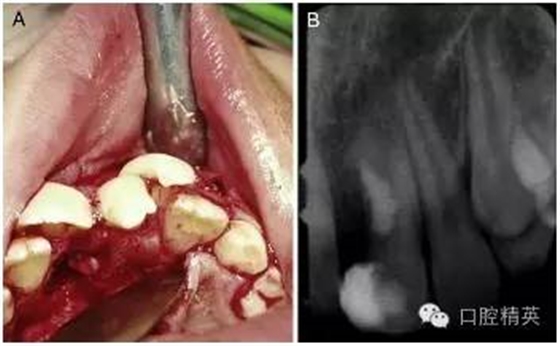

手術在局麻下進行,無術前用藥,也沒有對口腔進行其他特殊的術前準備。為了分牙的便利,患牙唇頰側的牙齦黏膜都被切至骨膜進行了徹底的翻瓣(圖 2-A)。

為了劈開牙冠和部分牙根,一把鋒利的骨鑿被順著牙長軸方向并稍向遠中傾斜地放置在了融合牙切端的發(fā)育溝中。在錘子的猛擊下,這顆過大牙齒的多生部分被逐漸劈離出來。按照術前計劃,并通過術中調整骨鑿的傾斜度,分離的剖面最終被止于齦下。

分牙過程中,在牙根中 1/3 處出現(xiàn)了一個 4mm 范圍的橢圓形的洞,通過洞可以觀察到暴露的牙髓。牙體牙髓醫(yī)生立即用 MTA 和調拌刀對這個洞進行了修補和拋光(圖 2-B)。翻瓣縫合之前,口腔外科醫(yī)生對尖銳的骨刺進行了修整,以便縫合后的牙齦黏膜能夠與硬組織緊密地貼合在一起。

圖 2 手術過程。(A)為了方便劈牙,對唇腭側牙齦黏膜做了徹底的翻瓣。(B)多生牙部分劈開拔除后和 MTA 蓋髓后的 x 線根尖片。